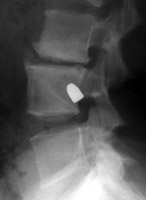

Tumbling Bullet Sign

Post traumatic bone cyst

Two sets of frontal and lateral radiographs, separated only by time, which reveal the "tumbling bullet sign"--which is simply a bullet which changes its location and orientation within a solitary bone cyst. This sign serves two purposes. It is documentation of the evolution of a solitary bone cyst as a corollary of trauma, and reveals the free movement of the foreign body within the confines of the lesion establishing its cystic rather than solid nature. It is similar to the fallen fragment sign.

- Click on the image for a larger versionA - Click on the image for a larger versionB - Click on the image for a larger versionC - Click on the image for a larger versionD